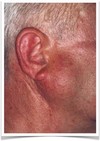

- Painless, slowly growing, firm enlargement

- swelling over mand ramus in front of ear

Warthin Tumor

- Exclusively in parotid gland

- Near mandibular angle